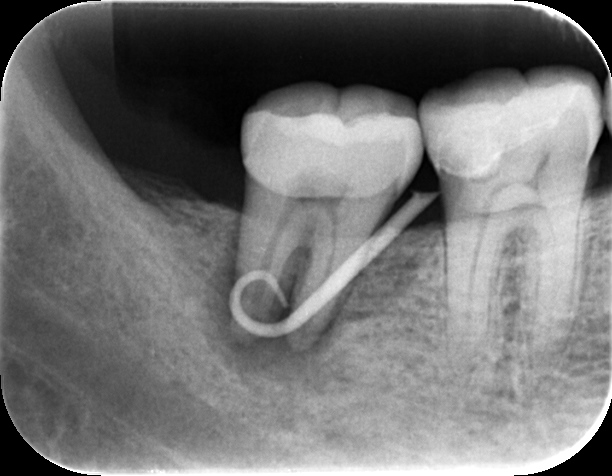

できものの出口からレントゲンに写るゴムを挿入して写真を撮ると、根の先で渦を巻いており、ここに膿の袋ができていることがわかります。